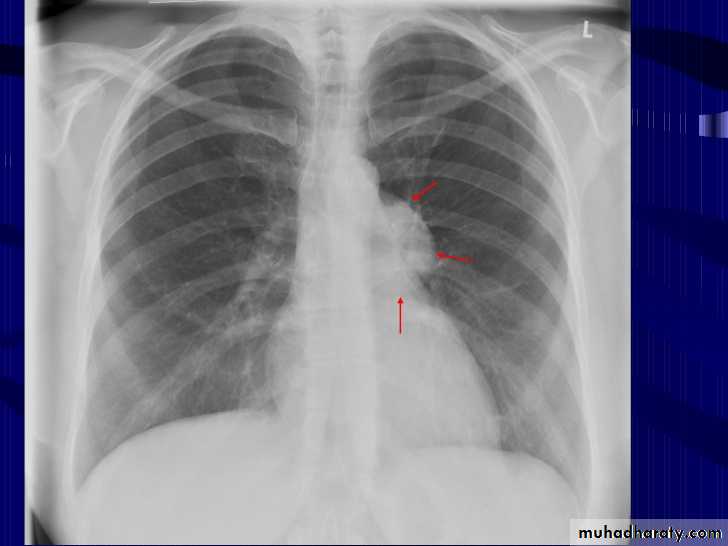

Hodgkin lymphoma of the middle mediastinum